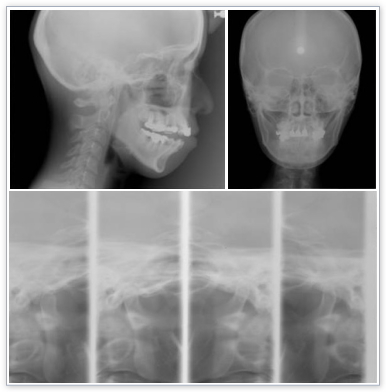

レントゲン(セファロ、顎関節撮影)

当院のレントゲンはデジタルレントゲンを採用していますので、被爆を最小限度におさえられます。